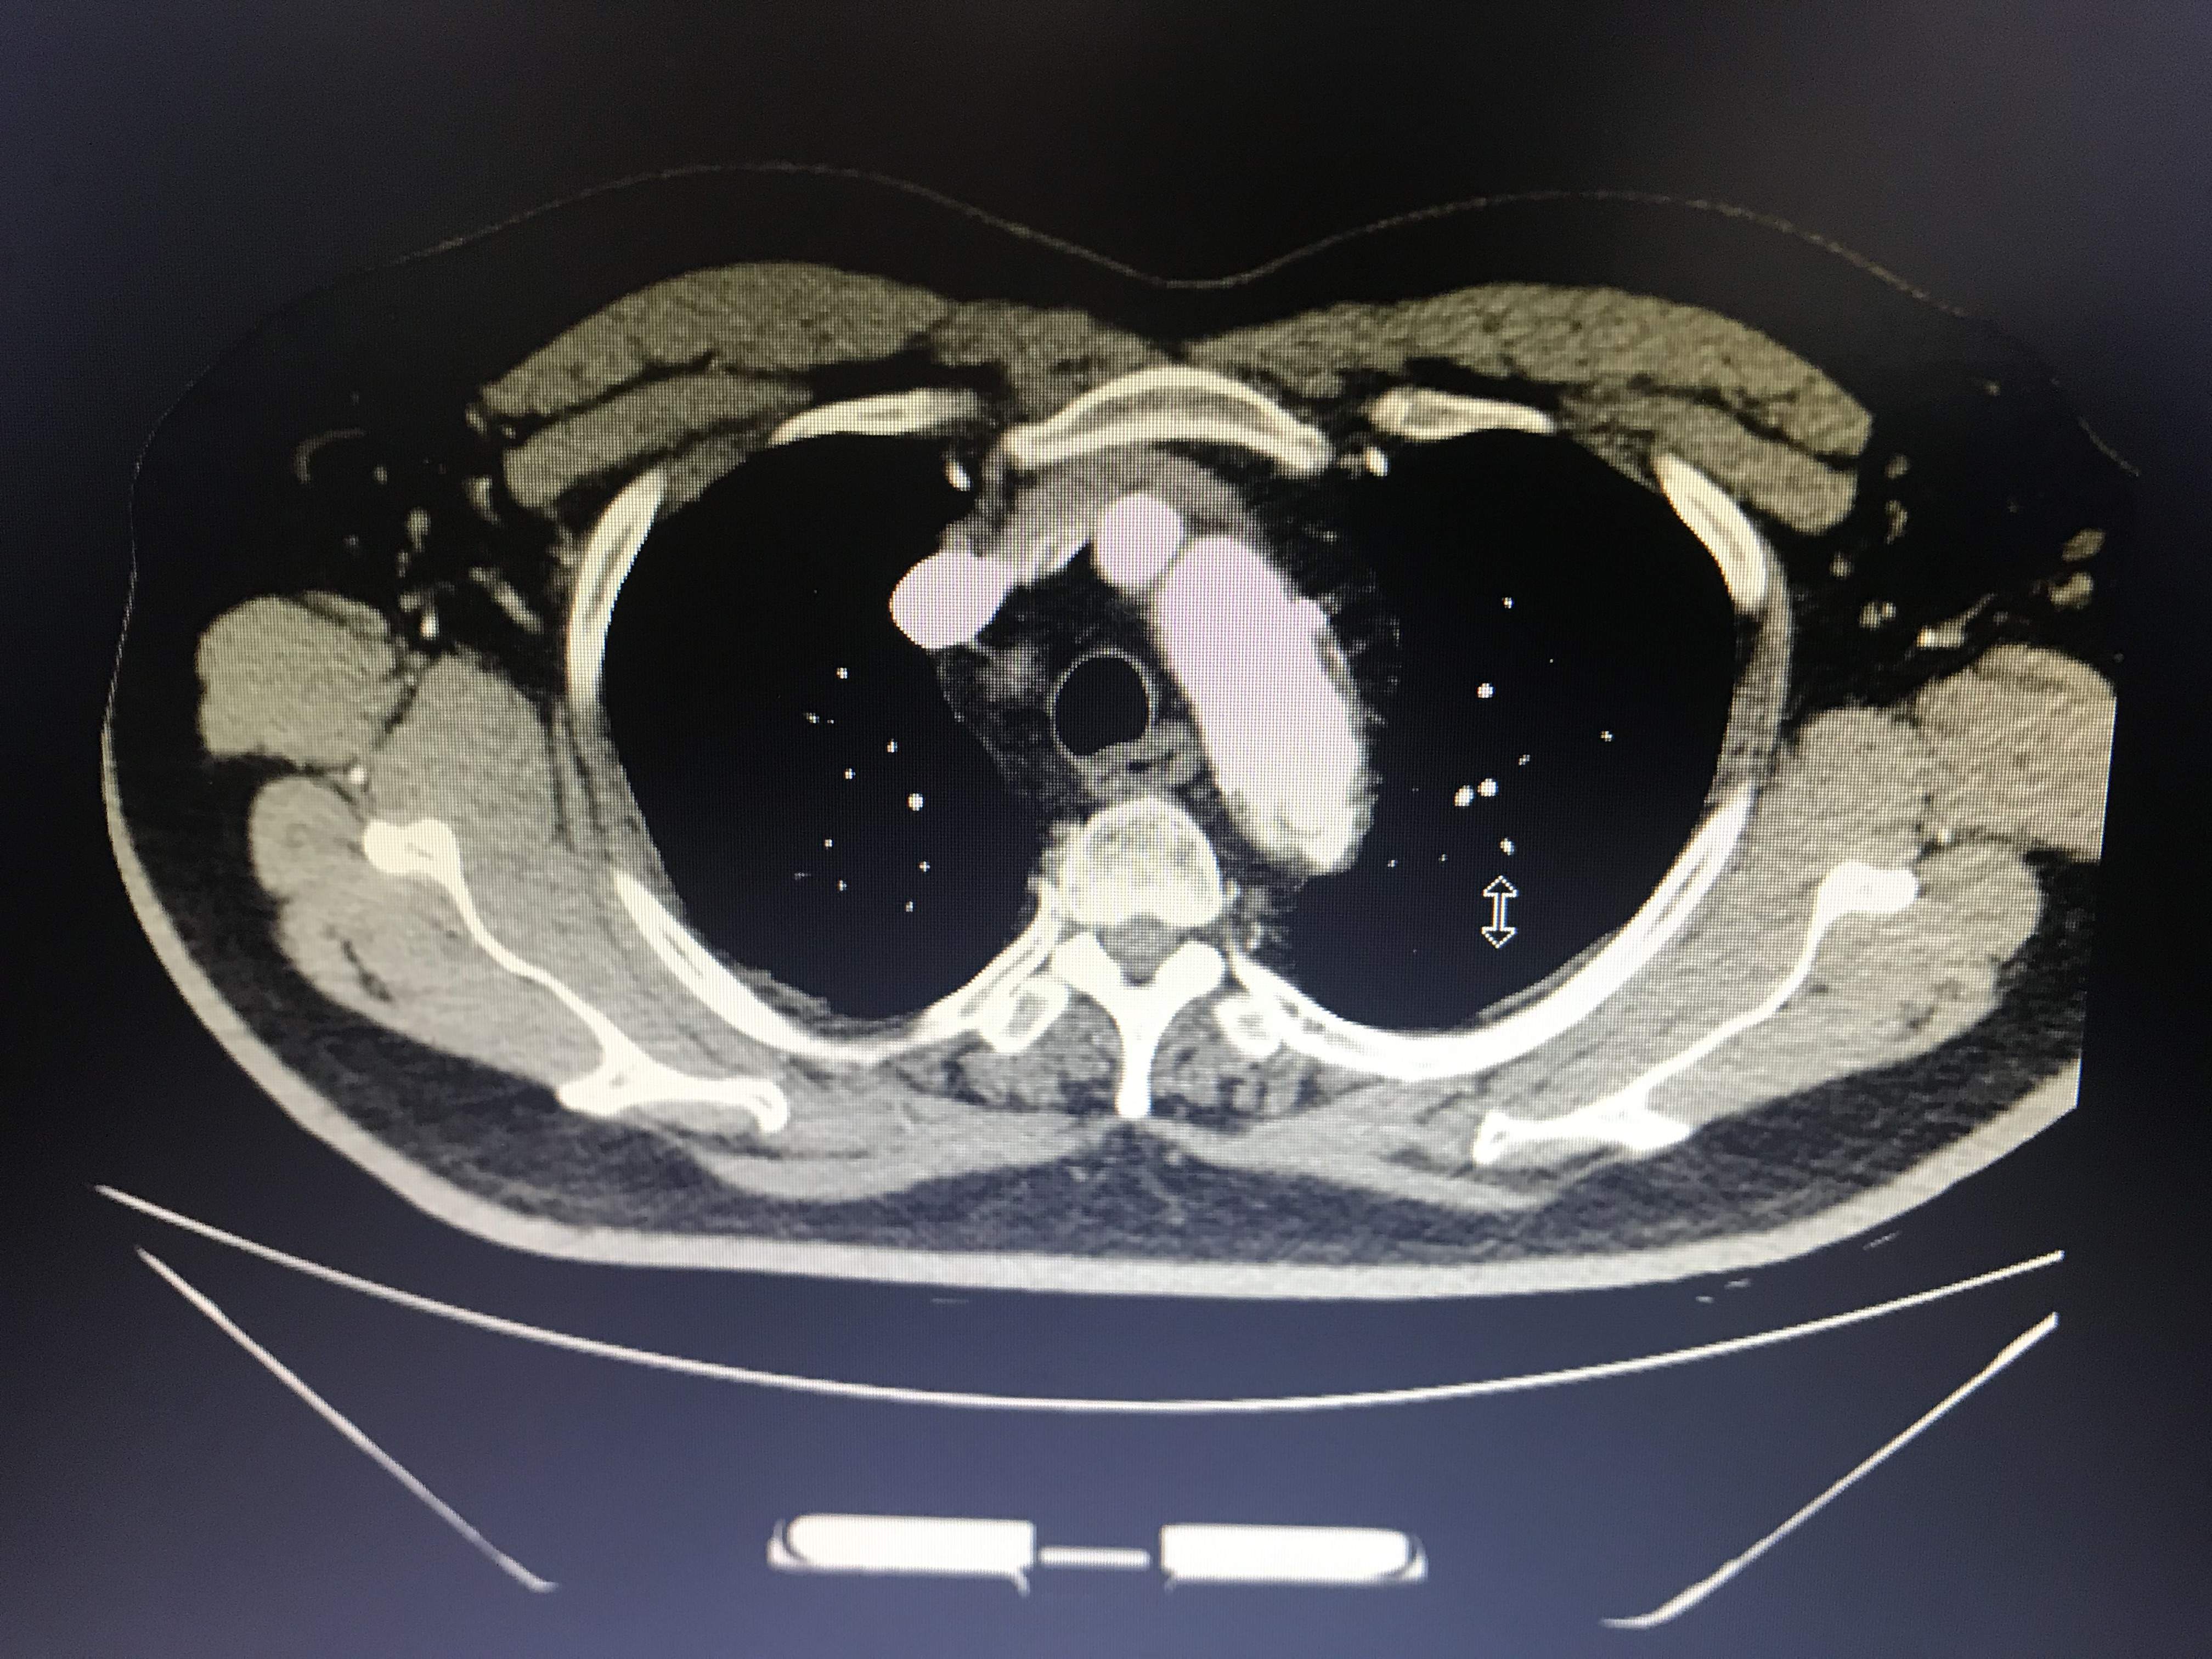

病人胸痛,这图像竟然不是主动脉溃疡?

大家帮我忙看看,到底是不是主动脉溃疡?